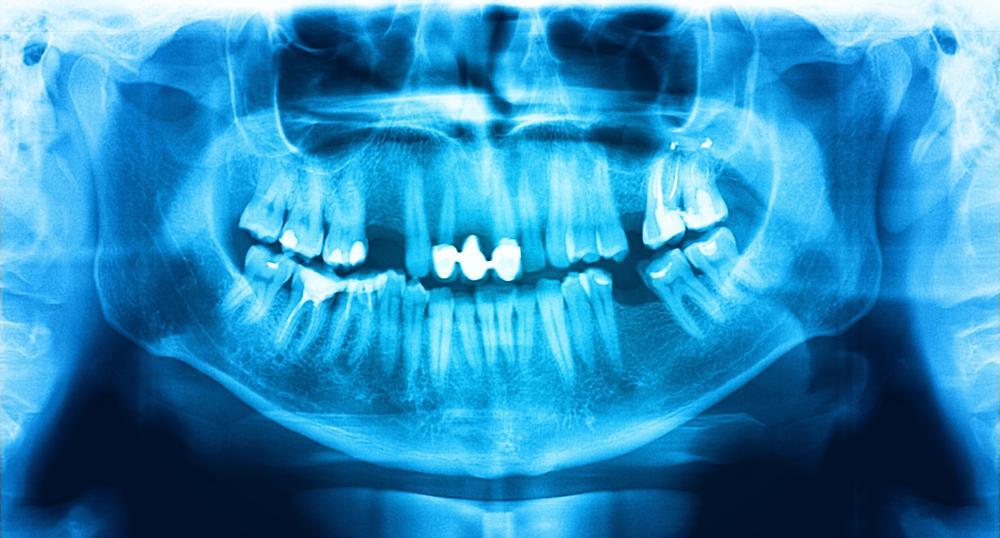

One of the most valuable treatments your dentist’s office provides is access to digital dental x-rays.

Why are dental x-rays so essential? Because they detect your dental decay early on—before it’s visible to the naked eye, and usually before you’re even symptomatic.

This early detection means that our Winston-Salem dentists, Dr. Pryor, can catch your cavities when they’re small, painless, and less expensive to treat. It’s easy and relatively fast to fill a minor cavity that’s just starting to develop. It’s much more challenging to treat a cavity that’s been spreading for years.

Without digital dental x-rays, we wouldn’t know about your cavities until they started causing you enough pain that you scheduled a dental appointment with us—and by that time, there’s a good chance you would need a tooth crown or even a root canal to treat the problem.

X-ray images allows our dentist to see beyond the surface of your smile and evaluate the insides your teeth and under your gums. In addition to showing us any developed cavities, the imaging will also draw our eyes to “pre-cavity” areas or any spots in your mouth that show potential for problems.

Our hygienists, along with Dr. Pryor, will examine your x-rays for any red flags or indicators of conditions like:

- Decay

- Impacted teeth

- Oral cancer

- Tooth infection

- Gum disease